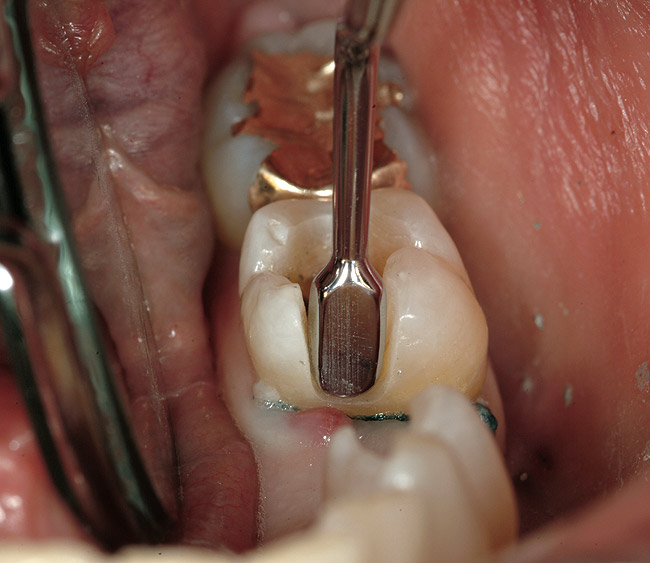

When fiber-reinforcing materials were introduced, the focus for their use was for periodontal splinting and stabilization resulting from tooth mobility.6,10,16,41-43 There is no doubt that splinting does reduce tooth mobility while the splint is in place.44 In the last decade, research supports the use of periodontal splinting as recommended therapy to stabilize those teeth to improve long-term prognosis.45-47 In a long-term clinical evaluation of splinting over a period of 48 to 96 months, using the original Ribbond Reinforcement Ribbon in fiber-reinforced composite resins was highly successful.17 The success of these splints can be attributed to close adaptation of the fiber ribbon to the tooth surface combined with cross stabilization of the mobile teeth by placing adhesive composite resin on the facial surfaces (Figure 4A, Figure 4B, Figure 4C, Figure 4D, Figure 4E).34,35 Splinting of traumatized teeth with fiber-reinforcing materials and adhesive composite resin has also been reported.48,49 When using fiber to stabilize the traumatized tooth or teeth or for tooth stabilization after re-implantation, the tooth must be allowed to have some movement and not be fixed in place.50,51

In vitro studies have demonstrated that the use of unidirectional glass-fiber reinforcement in the connector areas of FPDs contributes to significant composite reinforcement.29,36-38,66-68 Similar findings have been reported with a leno-weave UHMWPE and triaxial weave UHMWPE fiber.20,33,36 Fiber-reinforcing materials used by a dental laboratory are either resin pre-impregnated glass fibers, pre-polymerized composite resin surrounding glass fibers, biaxial braid UHMWPE, leno-weave UHMWPE, or a triaxial weave UHMWPE (Table 3). Typically, the preparation designs for the abutment teeth are inlay or onlay preparations (Figure 6A, Figure 6B, Figure 6C, Figure 6D). They are highly successful and can provide the patient with clinical service for more than 5 to 10 years.69 These restorations must be cemented using an adhesive resin technique with resin cements. Both etch-and-rinse adhesives with a self-cure or dual-cure composite resin cement or with a self-adhesive resin cement are indicated for cementing these restorations (Figure 7).36-38,70 Also, fiber-reinforcing materials are being used by dental laboratories in the fabrication of provisional restorations to reinforce and strengthen acrylic and composite-resin provisional materials.15,40,71